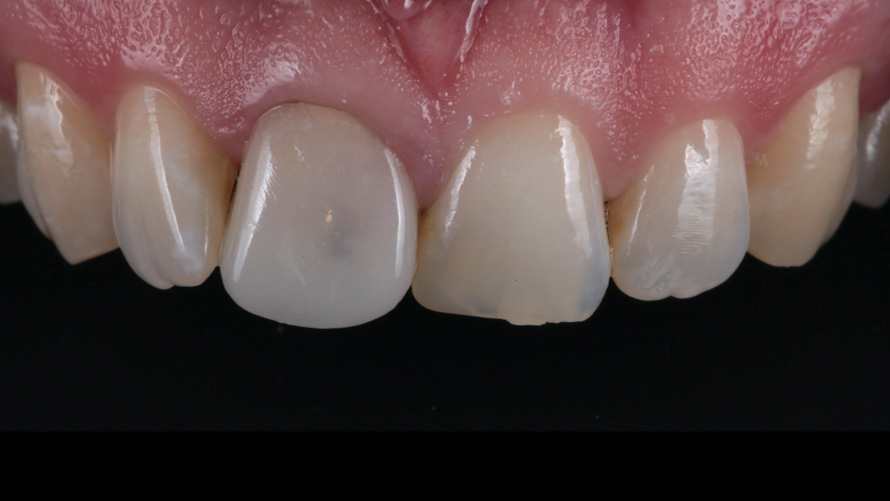

(16.) Case 2: Retracted full-smile view of the definitive all-ceramic restoration on the maxillary left central incisor.

Figure 16

Eight weeks after the initial start of the walking bleach procedure, the final layered lithium disilicate crown was tried-in and evaluated for function and esthetics. Upon patient approval, the intaglio surface of the crown was etched for 20 seconds with a 9.6% hydrofluoric acid etchant, rinsed, and then scrubbed with a 37.5% orthophosphoric acid solution to clean out any ceramic debris. The crown was then placed into an ultrasonic bath of 91% isopropyl alcohol for 5 minutes, after which the intaglio surface was coated with silane and placed under a warm air dryer for 1 minute. A translucent self-adhesive resin cement was used to bond the final restoration to the preparation. The patients both stated that they approved of the form, function, and esthetics of the definitive restoration and that they were very pleased with the final results (Figure 13 through Figure 18). Routine periodic evaluations and radiographs were scheduled to monitor their oral health and esthetics.